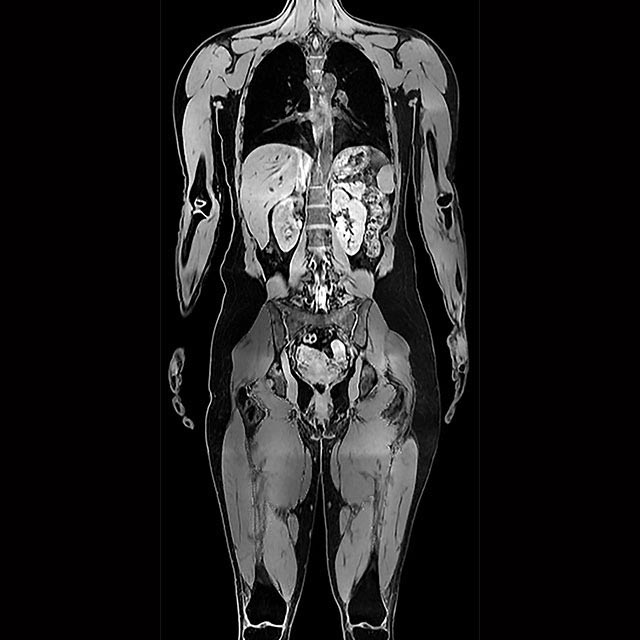

AMRA® BCP Scan

Understand your patient’s fat and muscle composition using MRI-based measurements within health and wellness.

Digital health made easy—You send us MR images, we send you easy-to-understand reports.